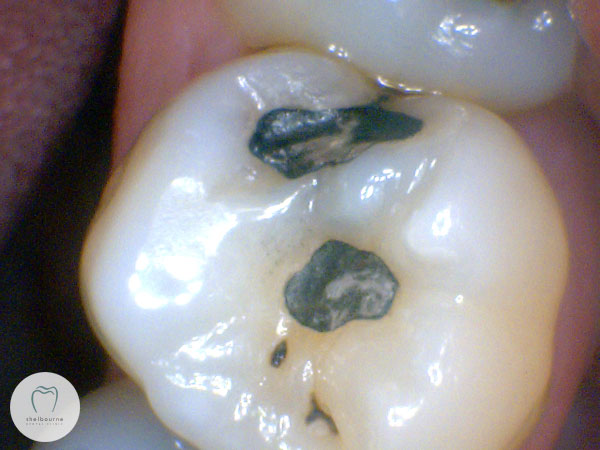

The patient, who I was seeing for the first time, reported significant pain from the upper left teeth. Nothing was obviously visible, no teeth were tender to pressure or biting. Here’s a photo of the area. Two small fillings in this tooth, but it looks fine.

So having found the damage, and numbed the tooth to ensure it’s not sensitive to the water spray, I polished out the existing filling and a small portion of tooth. You can quite clearly see the decayed area now. Unfortunately this decayed area just kept going, and the outlook for this tooth isn’t great.